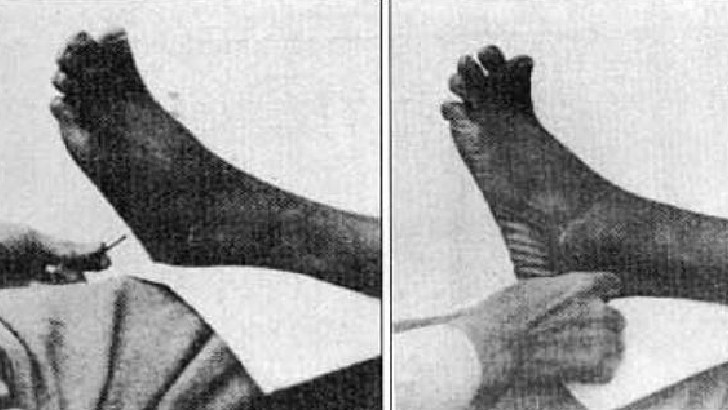

A reflex is which of the following?

Dilation and constriction of the pupils